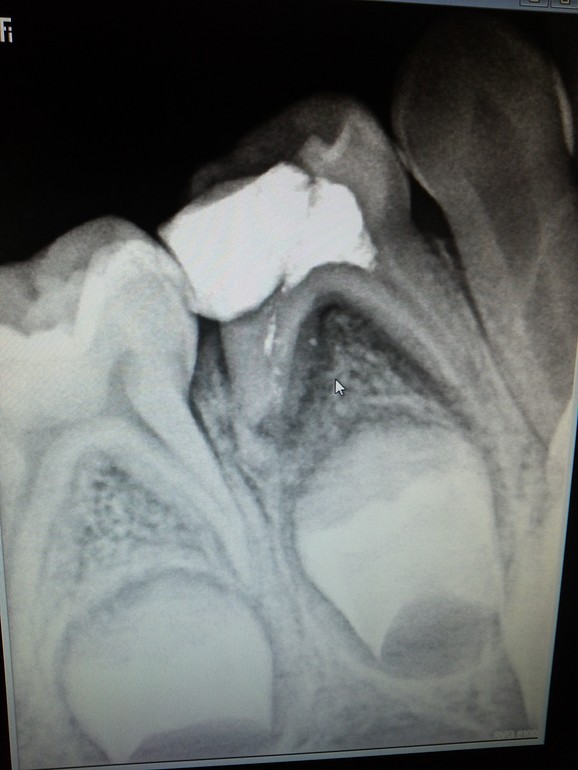

Срочно удалять?

Зуб 4-ка, летом лечили. Неделю назад заболел этот зуб, образовался гнойный

Мешок на дисне. Полоскали содой, прошло. Как поступить? Ждать, когда заболит, и идти удалять?